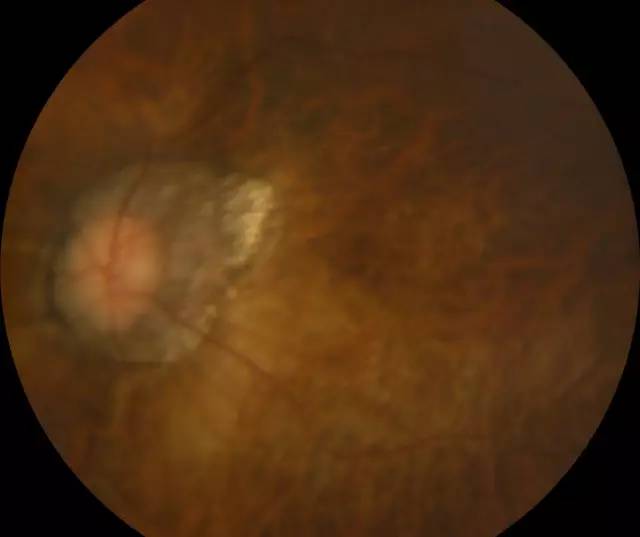

肖先生左眼术前眼底照相图

肖先生左眼术后眼底照相图